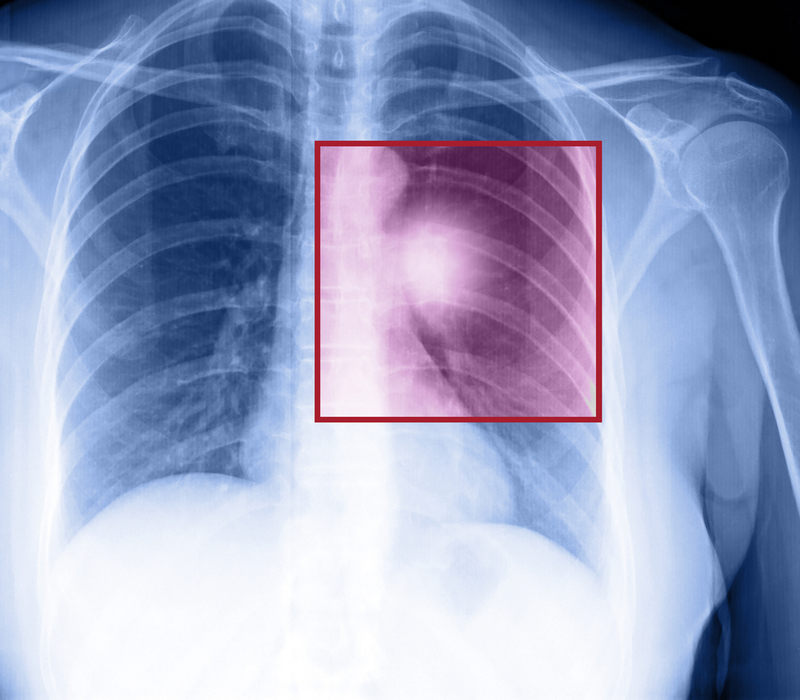

New type of lung cancer identified

Researchers have identified a new kind of small-cell lung cancer (SCLC) that may pave the way for developing personalised medicine approaches to target this previously unnoticed form of the disease.

According to the researchers, chemotherapy, radiotherapy, and surgery enable only 6 per cent of patients to survive five years from the time of their diagnosis and about 10 to 15 per cent of all lung cancers are SCLC. The study, published in the journal Genes and Development, suggests that an analysis of gene activity in human SCLC tumours reveals an unexpected activity pattern in around 20 per cent of samples.